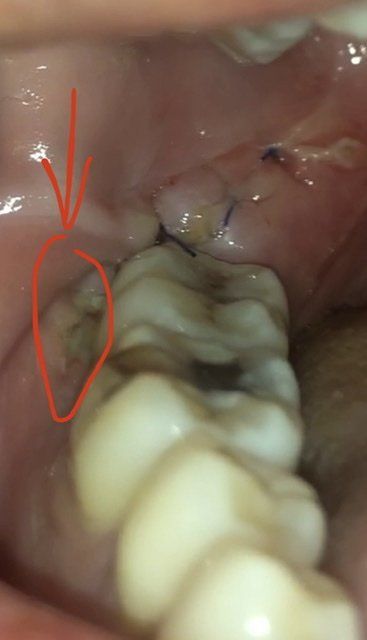

사랑니 매복 발치 3일 후인데 이게 뭔가요?

외국이라 의사에게 직접 물어보기 쉽지 않아 문의드립니다. 그저께 낮에 발치했는데요. 매우 큰 사랑니라서 많이 절개를 한거같아요. 오늘이 3일째 되는날인데 얼굴과 목이 더 부어서 걱정되어 이 안을 봤는데 이곳에 음식물이 낀건지 아니면 염증인건지 알고싶어요. 보통 어금니쪽 잇몸도 절개하나요?

현재 사진만으로 해당 부위의 염증 가능성을 판단하기는 어려워 보입니다. 다소 음식물처럼 보이는 면이 있으나 항생제 등을 복용중이신데도 해당 부위 통증, 부종 등이 심해진다면 감염의 가능성을 염두에 두어야겠습니다.

음식물 찌꺼기가 끼인게 아닌가 싶습니다.

붓기나 발적이 관찰되진않습니다. 염증이라기보다는 음식물 혹은 치석으로 사료되는 부분으로 관찰됩니다.

뒤에 봉합된 곳에도 고름이 관찰되는걸로 봐서는 고름이 흘러내린게 아닌가 생각됩니다.